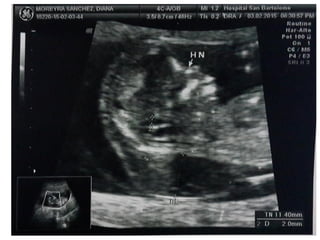

HUESO NASAL

• Corte sagital medio. Magnificación de la imagen.

• En esta posición tenemos que ver tres líneas :

– 1-2: 2 líneas paralelas más cercanas a la frente del feto,

la más externa corresponde a la piel y la más interna al

hueso nasal (de más grosor y ecogenicidad)

– 3: Otra línea a un nivel más alto que la piel que es la

punta de la nariz.

HUESO NASAL • Cortesagital medio. Magnificación de la imagen. • En esta posición tenemos que ver tres líneas : – 1-2: 2 líneas paralelas más cercanas a la frente del feto, la más externa corresponde a la piel y la más interna al hueso nasal (de más grosor y ecogenicidad) – 3: Otra línea a un nivel más alto que la piel que es la punta de la nariz.